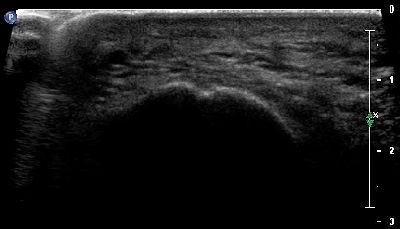

Cisti cisti 1